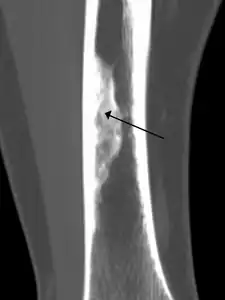

2. An ossified non-ossifying fibroma on CT

Diagnosis is by X-ray or MRI, usually when investigating a person for something else.[3] Medical imaging typically shows a well marginated radiolucent lesion, with a distinct multilocular appearance, sometimes looking like bubbles.[3] It is usually around 1-2cm in size, but be as large as 7cm.[4] They consist of foci consist of collagen rich connective tissue, fibroblasts, histiocytes and osteoclasts.[3] Usually no treatment is required.[4] Surgical curettage and bone grafting may be required if it is large.[4]

It is usually iagnosed by x-ray or MRI, when investigating another problem.[1] The tumor presents as a well defined radiolucent lesion, with a distinct multilocular appearance, sometimes looking like a "soap bubble".[2] If small and no symptoms, then biopsy is not needed.[1]